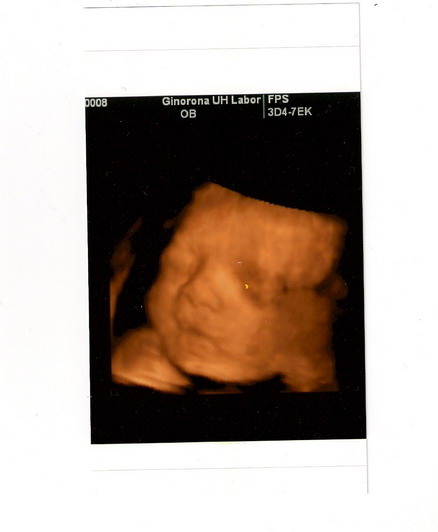

Köszönöm, hogy érdeklődtök, a babák nagyon jól vannak, szépen fejlődnek egy kiló körüliek.